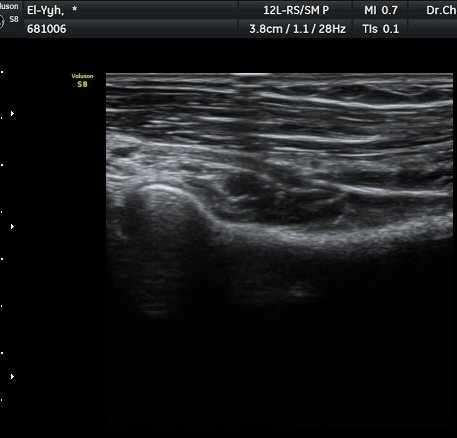

ÃÊÀ½ÆÄ °Ë»ç